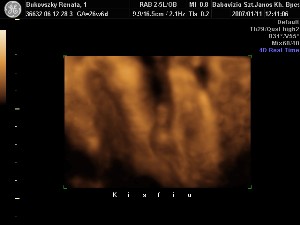

a bal szeme előtt a bokája van

a bal szeme előtt a bokája van

a lába mindig az arca előtt van

a lába mindig az arca előtt van